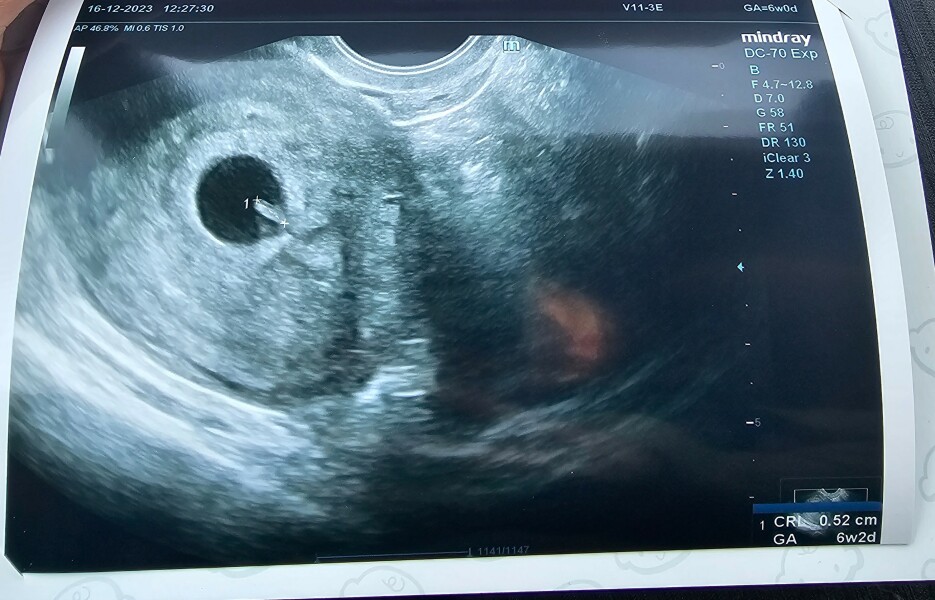

Hi ladies. Been stalking you all for a bit 😊 I tested positive really early, nearly 3 weeks ago now, I'm 6+0 and original EDD 10.08.24. I've been for an early scan this morning 🥰 baby is in the right place, measuring 2 days ahead so 6+2 & a nice little flicker of heartbeat ❤️ this is my second baby, little boy is 5!